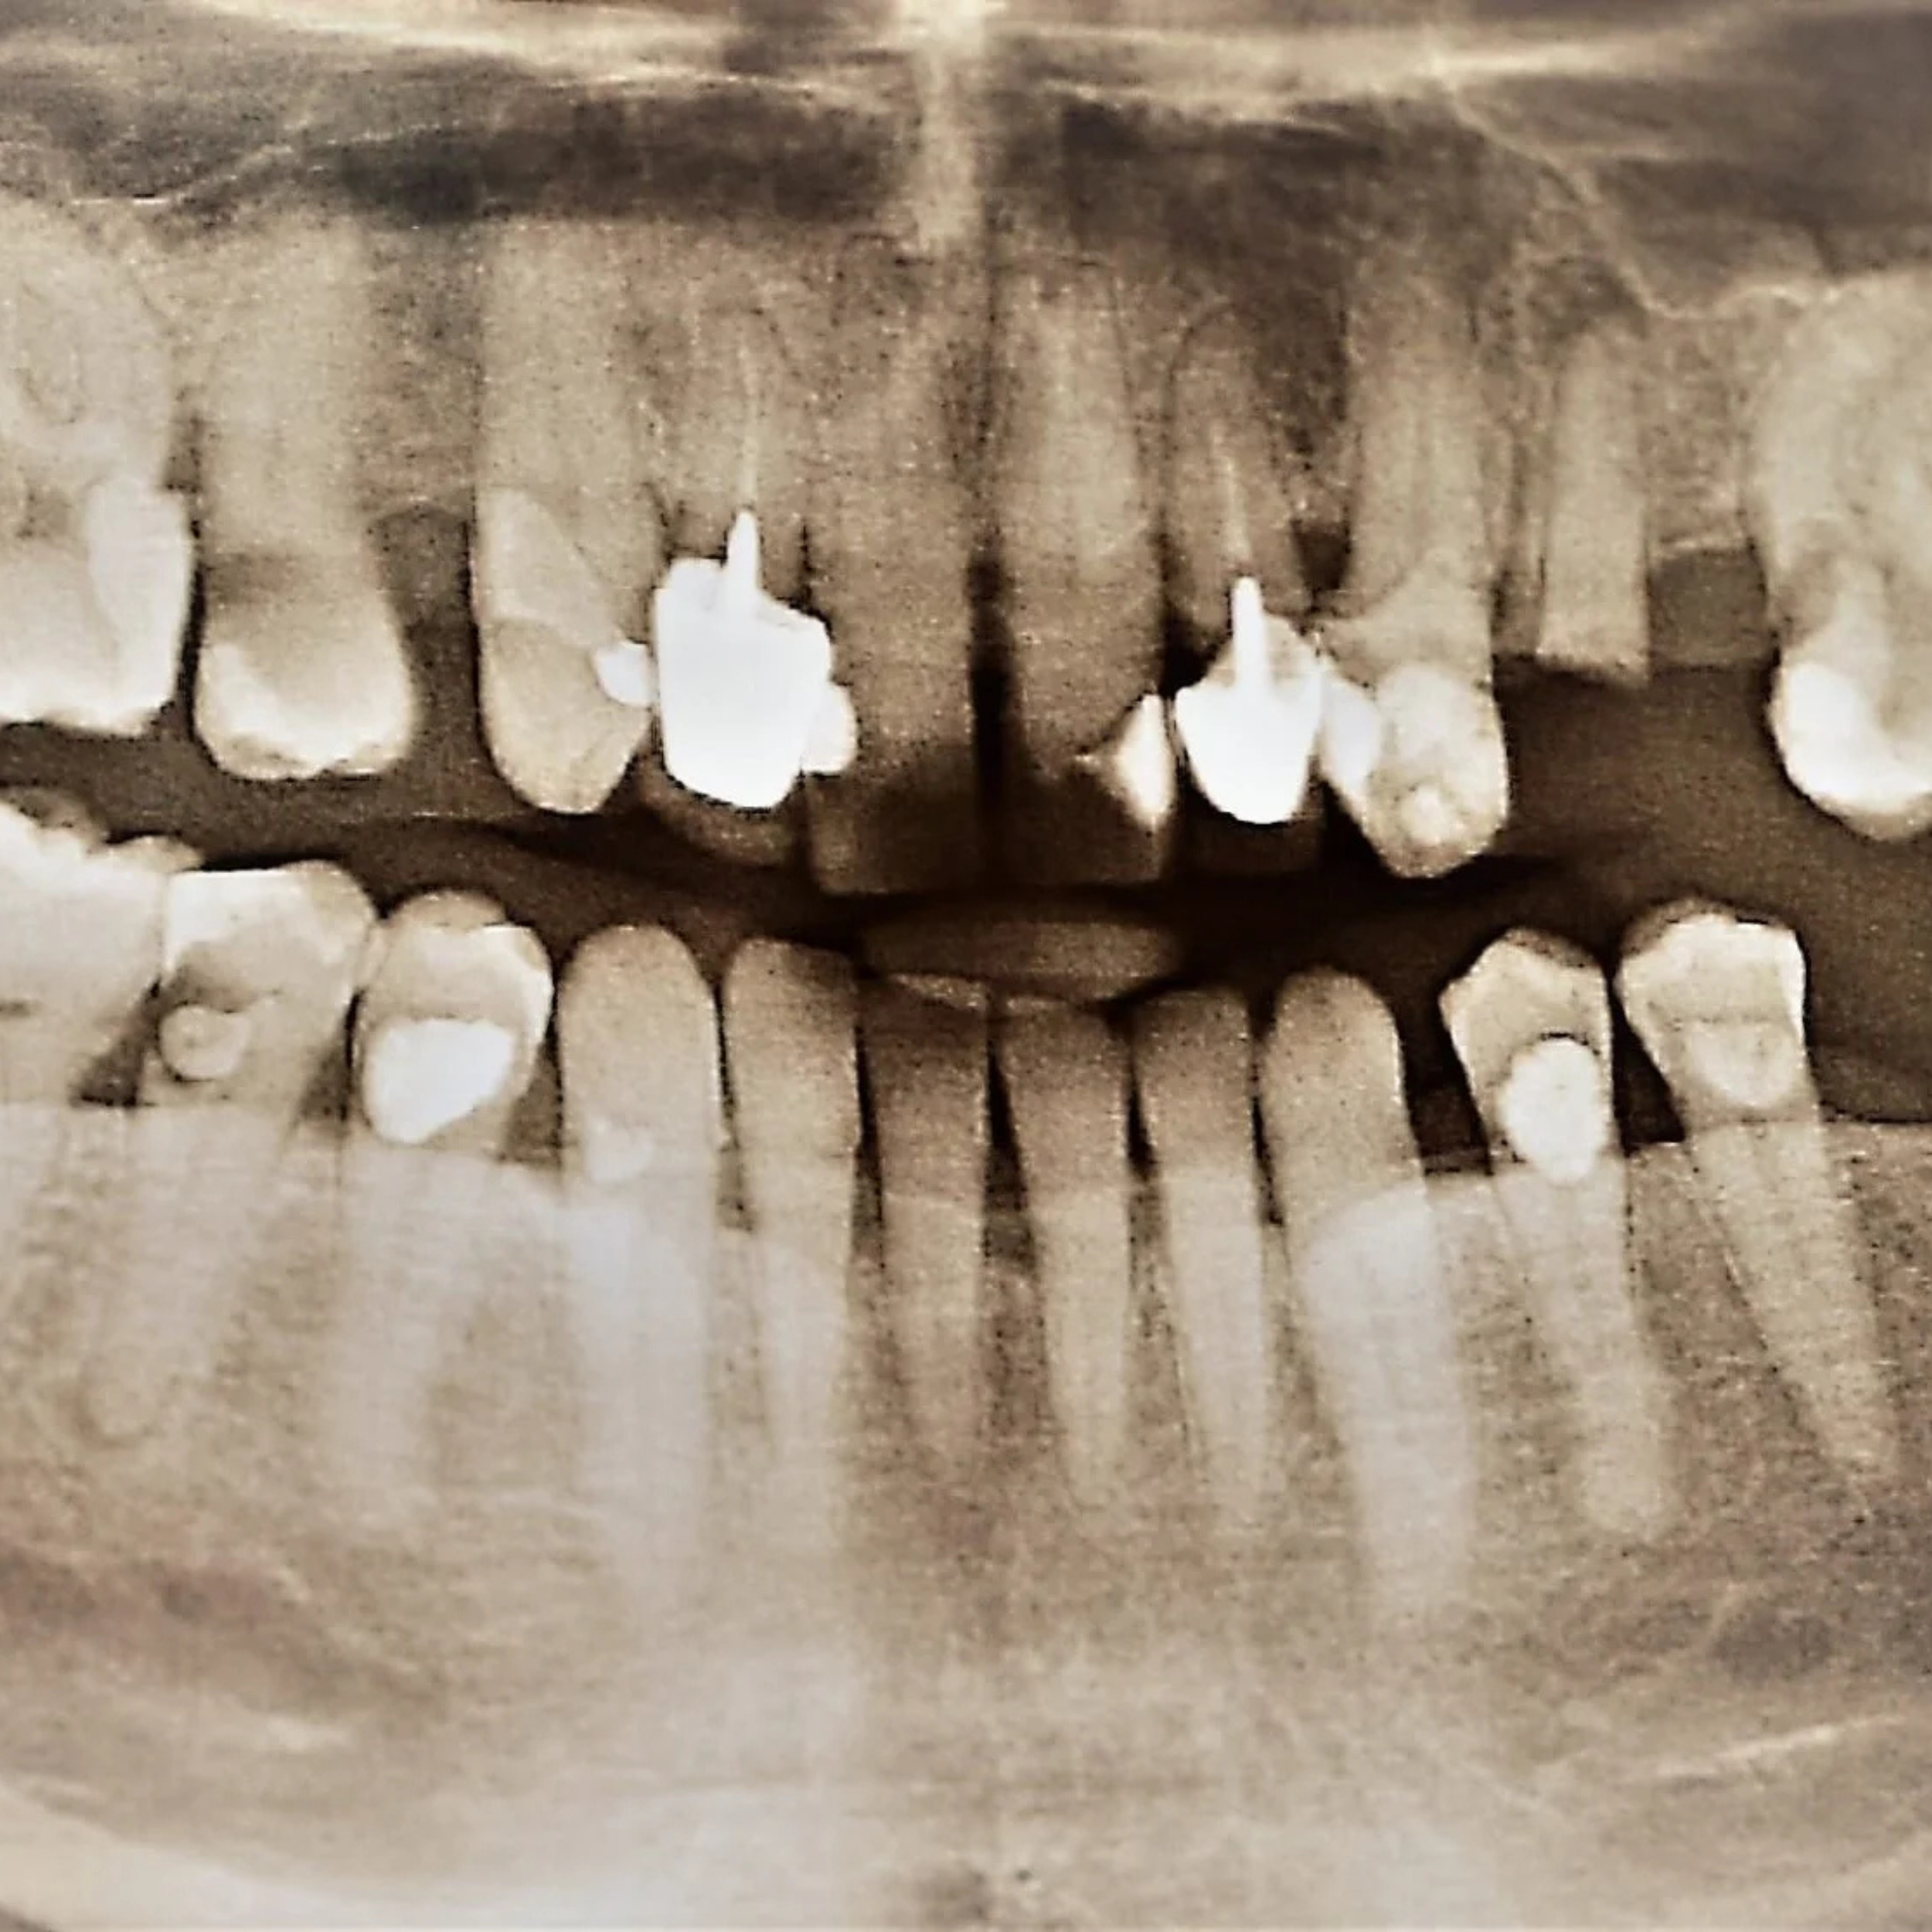

Implant Placement and Simultaneous Bone Grafting in the Aesthetic Zone